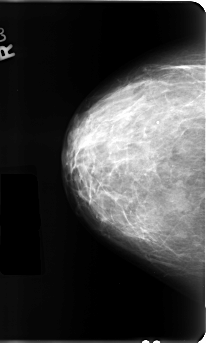

B_3111_1.RIGHT_CC

RIGHT_CC LINES 4792 PIXELS_PER_LINE 2880 BITS_PER_PIXEL 12 RESOLUTION 50 NON_OVERLAY